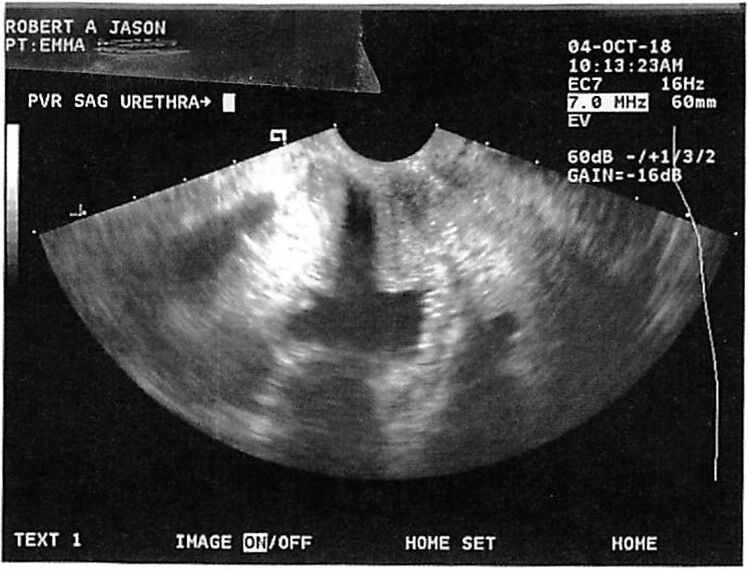

Before and after ultrasound images of the

urethral muscular tube show a remarkable transformation—from a dilated to a rejuvenated, tightened structure—demonstrating the proven effectiveness of

ThermiVa® in treating

Urinary Stress Incontinence (USI).

This improvement results from

targeted radiofrequency energy that strengthens and contracts the tissues surrounding the urethra, leading to

better closure, control, and continence—all without surgery.